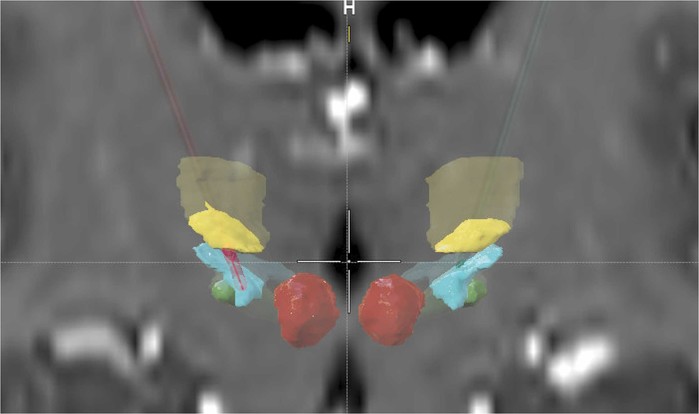

| ▲ 활성 접촉(분홍색) 위치. 왼쪽(빨간색)과 오른쪽(녹색) 이식 리드는 융합 T1 MRI 스캔의 관상면 단면에 표시되어 있으며, 활성 전극은 분홍색으로 표시돼 있다. VIM(노란색), 불확정대(파란색), STN(녹색), 그리고 빨간색 핵(빨간색)은 자동분할되었습니다. 투명한 색상은 관상면 단면 외부에 있는 피질하 핵 또는 리드의 범위를 나타낸다. 활성 전극은 기저 VIM 영역으로 돌출되어 있으며, 전극 끝은 시상하부 영역인 불확정대에 도달한다. (출처: Journal of Fluency Disorders

Left thalamic deep brain stimulation for persistent developmental stuttering / September 2025, Journal of Fluency Disorders) |